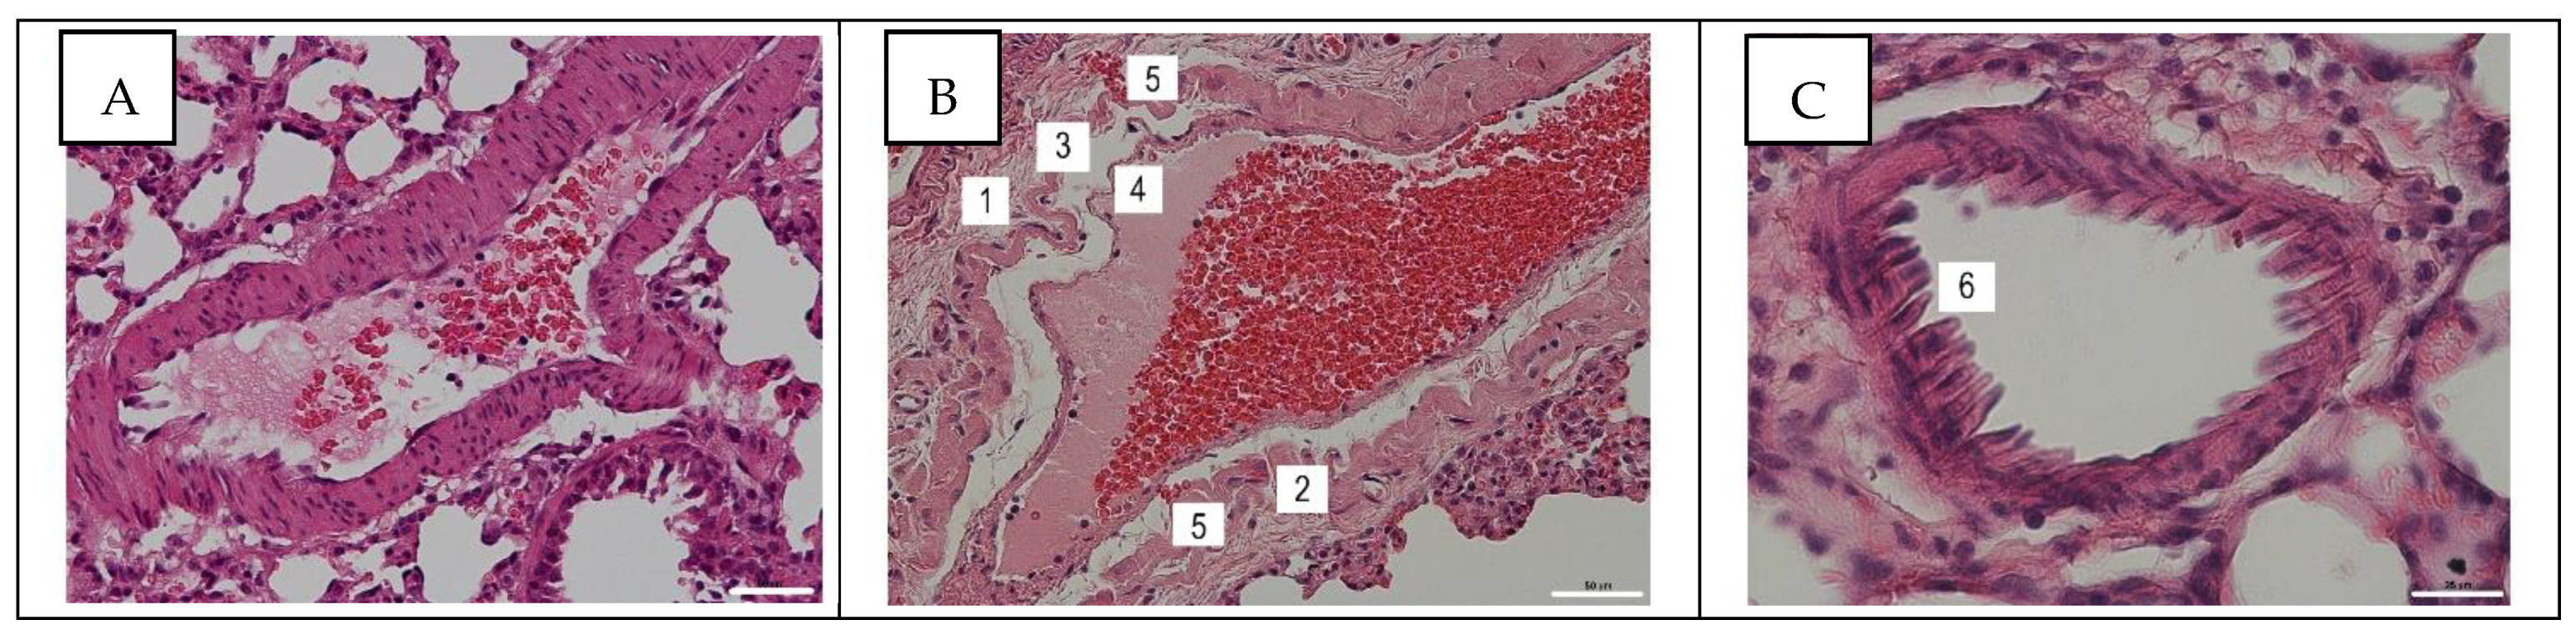

3.3. Histological Assay of Pulmonary and Mesentery Blood Vessels

3.4. Detection of Influenza A Virus NP Antigen in Pulmonary and Mesenteric Tissues and Blood Vessels